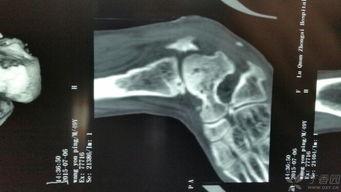

在手术之前,医生会先给你做一系列的检查,确保你的身体状况适合进行手术。这个过程可能包括X光、CT扫描或者MRI,以便医生能够清楚地看到你的脚踝骨骼情况。视频中的医生在手术前详细地介绍了这些检查的重要性,以及它们如何帮助确定手术方案。